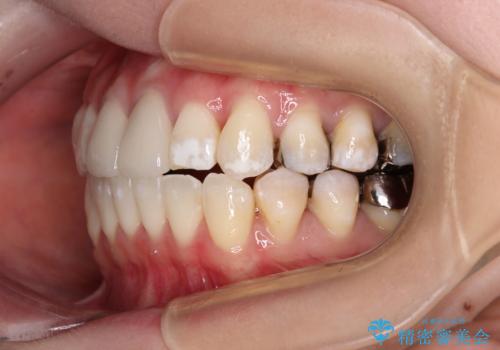

- 前歯のデコボコとセラミッククラウン周りの黒い縁を気にして来院された患者様です。

ワイヤー装置、マウスピース、どちらの装置でも治療は可能でしたが、マウスピース矯正の自己管理の煩わしさを懸念され、ワイヤー装置にて矯正治療を行うこととしました。

前歯の黒い縁は、矯正治療後にオールセラミッククラウンにて改善することとしましたが、いち早く目立たなくしたいとのことで、事前に矯正治療用仮歯に置き換えてから矯正治療を開始しました。